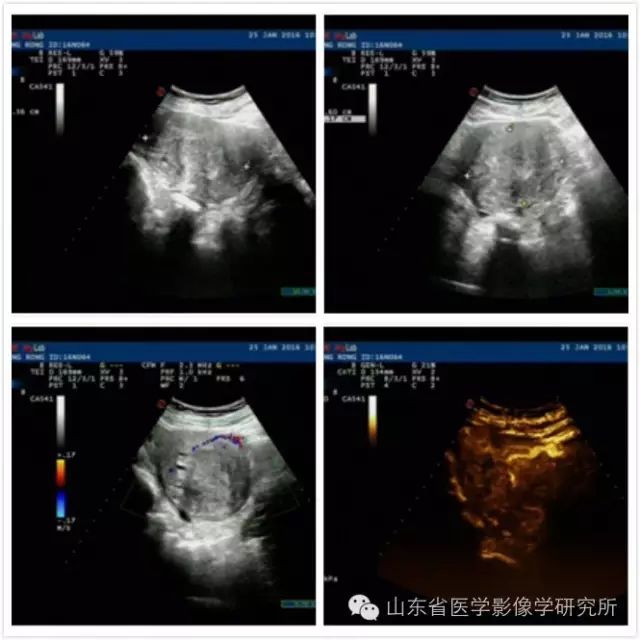

一位41岁的女性患者,发现巨大子宫肌瘤5年,并伴有月经量增多、痛经近1年,给她带来了极大的痛苦。 由于她做过剖腹产手术,她想做手术治疗子宫肌瘤。 治疗肿瘤必须将子宫彻底切除,这是一种侵入性很大的手术,会给患者带来巨大的身体和心理创伤。 患者来我科就诊。 经过我们团队的精心准备,在局麻下完成了巨大子宫肌瘤的微波消融治疗,正常子宫组织得到了完全保护。 没有发生重大并发症。 患者术后1周出院。 。

▲术前超声检查和超声造影检查,确定肌瘤大小,准确定位供血动脉位置

▲消融后MR检查证实肌瘤已完全消融